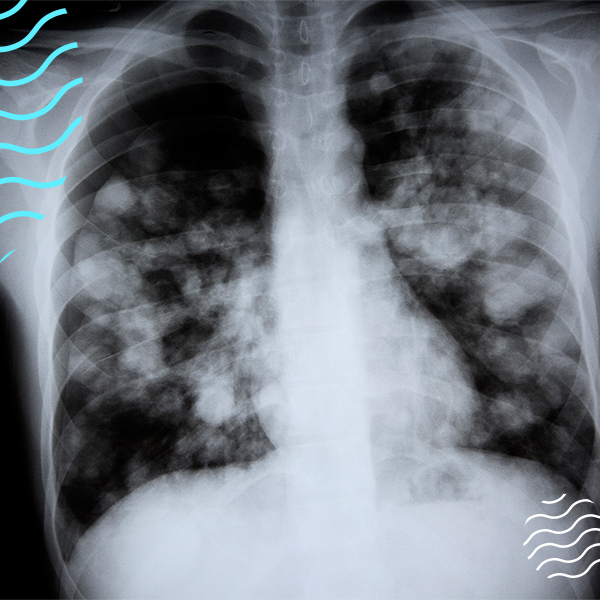

Doctors have seen thousands of vape-related hospitalizations, including severe breathing problems, pneumonia, and over 65 deaths—including a 15-year-old.